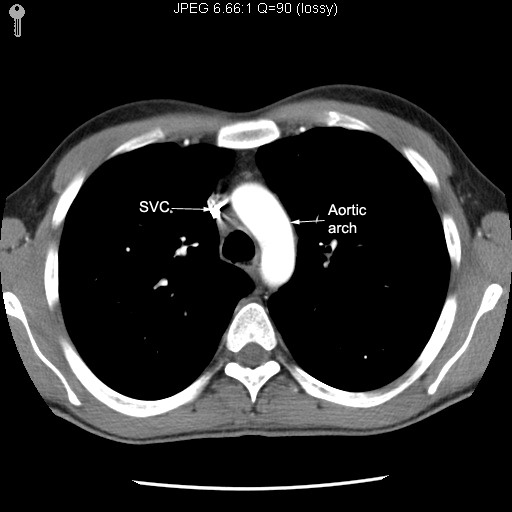

Arch of Aorta

- Begins at the level of the upper border of

the second sternocostal articulation on the right side

- Arches upward, backward, and to the

left in front of the trachea .

- At the lower border of fourth thoracic

vertebra it becomes the descending aorta.